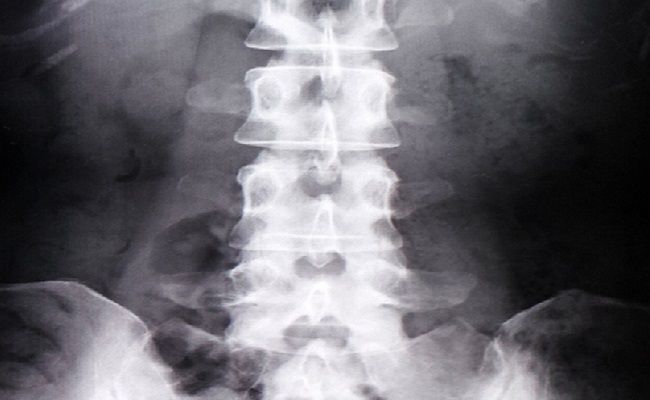

そして、診察後に骨密度を測りに放射線科へ移動し、人生初の骨密度検査を受けました。ベッドにあお向けに寝て、台の上に足を乗せます。腰の辺りから上半身をX線でスキャンするといった測定方法です。

2〜3分ほどで終わり、骨密度の結果もすぐにプリントしてもらえました。結果を見ると46歳の今、骨密度は同年齢の平均値でしたので、とても安心しました。しかし、20代の平均値と比べると77%ほどとのことで、年齢とともに骨密度が低くなっていることを知ったのです。